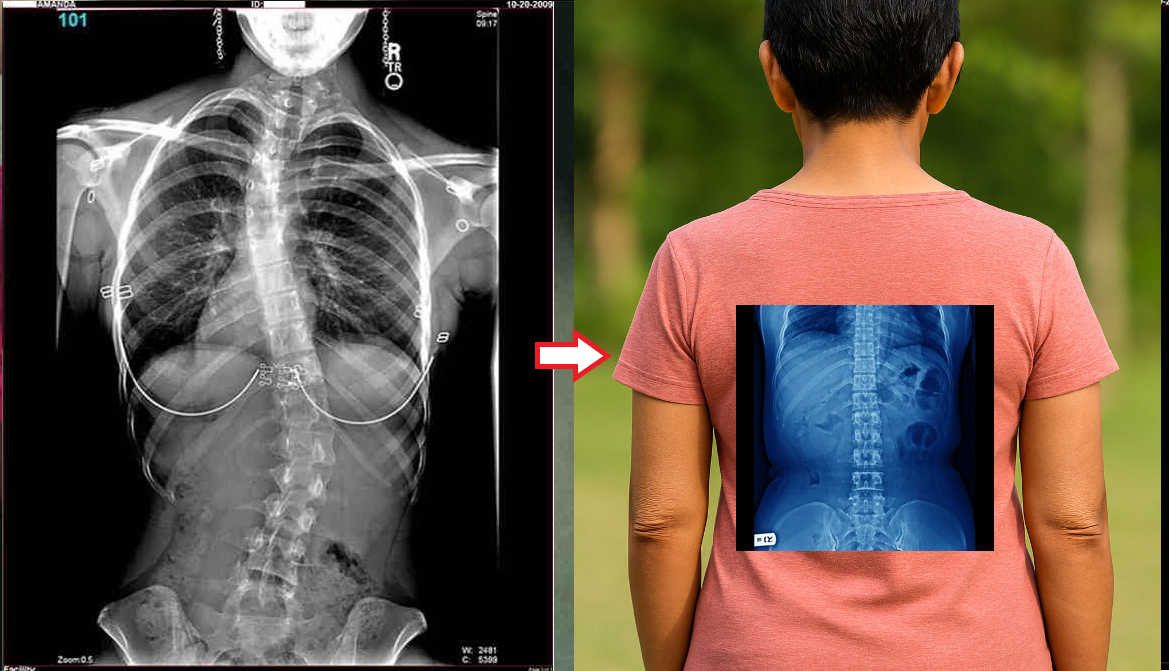

Wanita, 62 tahun. Pergeseran tulang belakang yang parah. "Jointlite" berhasil memulihkan tulang belakang sepenuhnya dalam 90 hari.

Pria, 37 tahun. Koreksi total postur tubuh dengan "Jointlite" selesai dalam 1,5 bulan.

Wanita, 51 tahun. "Punggung bungkuk janda" dan deformasi tulang belakang. Benjolan sepenuhnya hilang dalam 60 hari penggunaan "Jointlite".

Produk ini menyelamatkan saya dari skoliosis dan nyeri punggung! Pekerjaan yang banyak duduk dan osteochondrosis sangat menyiksa, dokter pun menyerah, tetapi Jointlite benar-benar menyelamatkan saya! Skoliosis dan deformasi tulang belakang itu mengerikan! Lebih baik merawatnya sebelum terlambat. Ini hasil yang saya dapatkan: